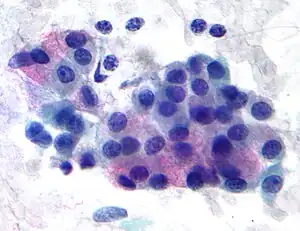

| Micrograph of a mucoepidermoid carcinoma. FNA specimen. Pap stain. | |

In terms of diagnosis we find that histological staining, radiological imaging and molecular diagnostic features all play a role in the evaluation[1] This tumor is not encapsulated and is characterized by squamous cells, mucus-secreting cells, and intermediate cells.[7]